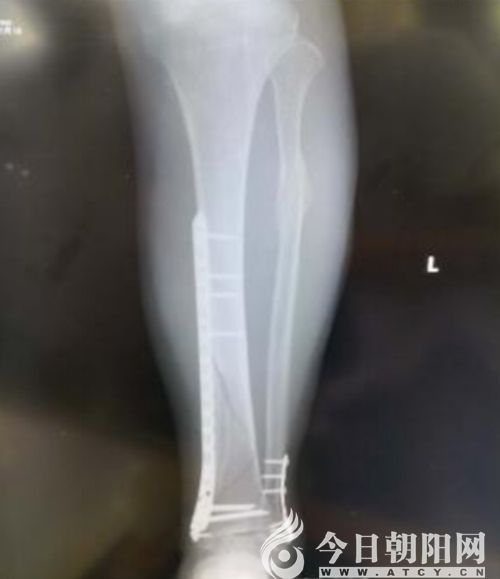

術(shù)后X線

隨著社會(huì)的進(jìn)步與發(fā)展,人們對(duì)外傷骨折的治療要求越來(lái)越高,朝陽(yáng)市中心醫(yī)院骨外三科結(jié)合大量臨床經(jīng)驗(yàn),積極探索引進(jìn)了微創(chuàng)經(jīng)皮鋼板內(nèi)固定(MIPPO)技術(shù)。運(yùn)用“內(nèi)支架”概念進(jìn)行骨折固定,用鋼板對(duì)骨折行橋接固定,利用肌腱復(fù)位作用及間接復(fù)位技術(shù)進(jìn)行骨折復(fù)位。

朝陽(yáng)市中心醫(yī)院骨三科主任胡剛介紹:“骨折治療的目的是盡早使肢體功能恢復(fù)到受傷前的水平以及減少并發(fā)癥的發(fā)生。與傳統(tǒng)開(kāi)放式骨折治療方法相比,MIPPO技術(shù)遠(yuǎn)離骨折部位進(jìn)行復(fù)位,為骨折愈合、軟組織修復(fù)提供良好的生物學(xué)環(huán)境,能最大程度地保護(hù)骨折處血供,促進(jìn)骨折愈合,減少感染和再骨折的危險(xiǎn)性,維持骨折穩(wěn)定性。MIPPO技術(shù)在我科的成功應(yīng)用,充分證明了我院骨科人攻堅(jiān)克難的能力與決心,我們將不斷探求微創(chuàng)新技術(shù),更好地造福朝陽(yáng)百姓。”